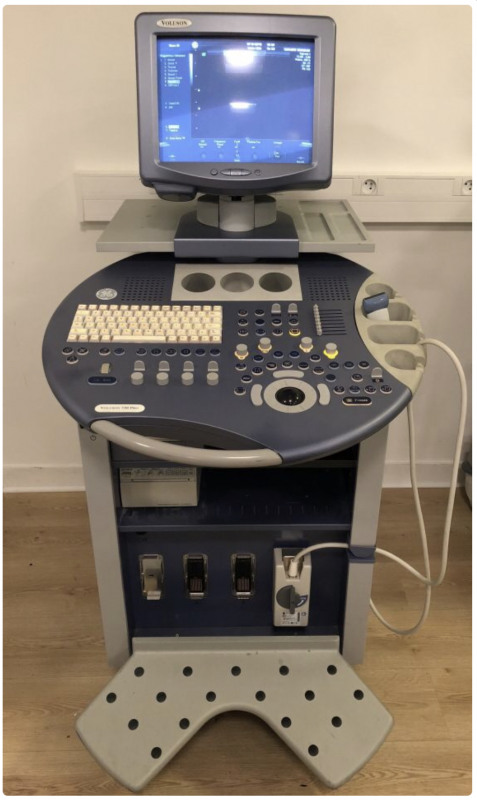

Медицинская Техника: УЗИ с Ge Voluson 730 Expert